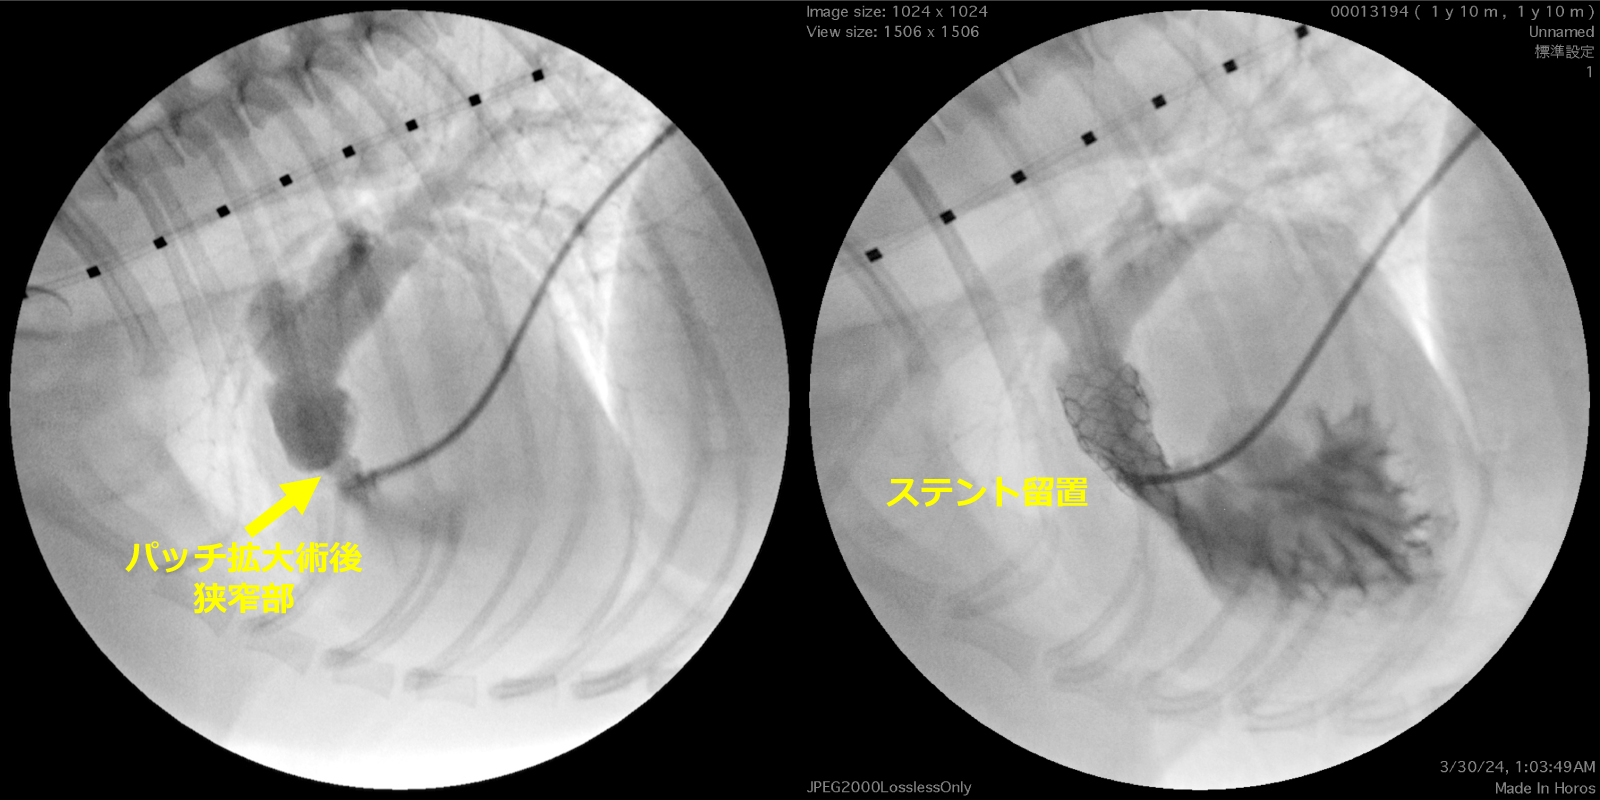

ステント留置後、臨床症状の改善を確認